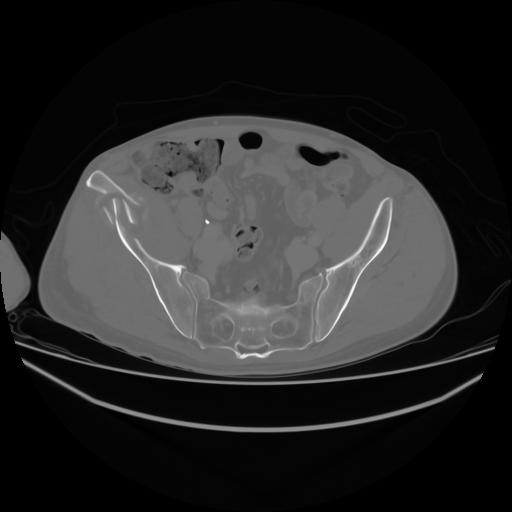

4 CUERPO,CE,Axial,3.0,CUERPO,,